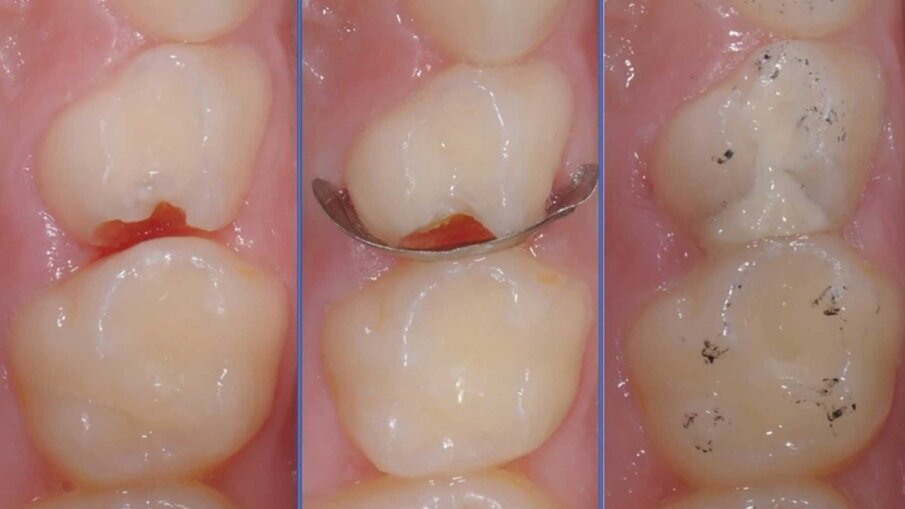

Riservato a lesioni moderate e avanzate, consiste principalmente (ma non solo) nel trattamento restaurativo diretto eseguito in modalità atraumatica o convenzionale attraverso il principio della rimozione selettiva della lesione cariosa. Storicamente la fase di rimozione della dentina è da sempre stata intesa come non selettiva (o totale) ossia che si conclude solo allorquando si raggiunga la cosiddetta dentina “dura” (hard dentine) aumentando quindi il rischio di esposizioni iatrogene pulpari. In odontoiatria pediatrica sarà suggeribile quindi limitarsi a una rimozione selettiva (o parziale) ossia che si conclude nel momento in cui si raggiunga la cosiddetta dentina “affetta” (ma non infetta) di consistenza intermedia tra la dentina dura e la dentina rammollita (Leathery & Firm dentine). È evidente come questa distinzione intraoperatoria sia tutt’altro che semplice e oggettiva da eseguire; a questo proposito è crescente l’evidenza a supporto della rimozione chemio-meccanica della lesione cariosa, ovverosia sull’ausilio di un mezzo chimico (a base di ipoclorito o di enzimi derivati dalla papaina) in grado di facilitare l’operatore durante questa delicata procedura8 (Fig. 2).

Come anticipato, il principio di rimozione selettiva è alla base del processo restaurativo che potrà essere eseguito in modalità atraumatica o convenzionale. Per quanto riguarda le modalità restaurativa atraumatica, questa fu introdotta da Frencken negli anni 90 e consisteva nell’utilizzo esclusivo di strumenti manuali nella fase di rimozione selettiva della lesione cariosa, e di cementi vetroionomerici polvere-liquido nella fase di restauro, il tutto senza ausilio di anestetico locale e isolamento assoluto del campo operatorio. Ad oggi esistono diverse varianti.

In termini di rimozione della lesione cariosa queste varianti consistono nell’utilizzo singolo o congiunto di:

- strumenti meccanici (rotanti, oscillanti);

- mezzi di rimozione chemio meccanica della carie (a base di ipoclorito di sodio o derivate dalla papaina);

- meccanismi di disinfezione chimica (SDF, Ozono) e luminosa (laser);

- foto-ablazione (laser).